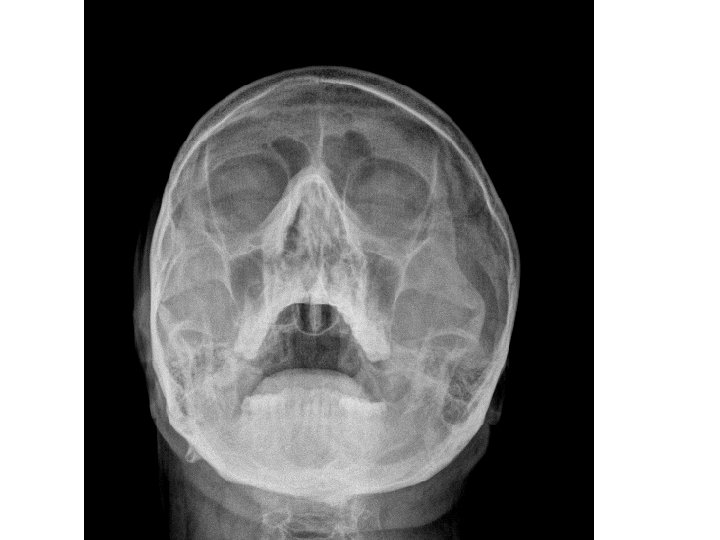

EXTERNAL NOSE • External nose is shaped like a pyramid with its root up and base directed downwards. • Consists of osteocartilagenous framework covered by muscle and skin.

• • Osteocartilagenous framework: Upper 1/3 rd - bony Lower 2/3 rd – cartilagenous Bony framework a) Nasal bones b) Nasal processes of frontal bone c) Frontal processes of maxilla

• • • Cartilagenous framework a) Upper lateral cartilages b) Lower lateral cartilages (alar cartilages) c) Lesser cartilages (sesamoid cartilages) d) Septal cartilage